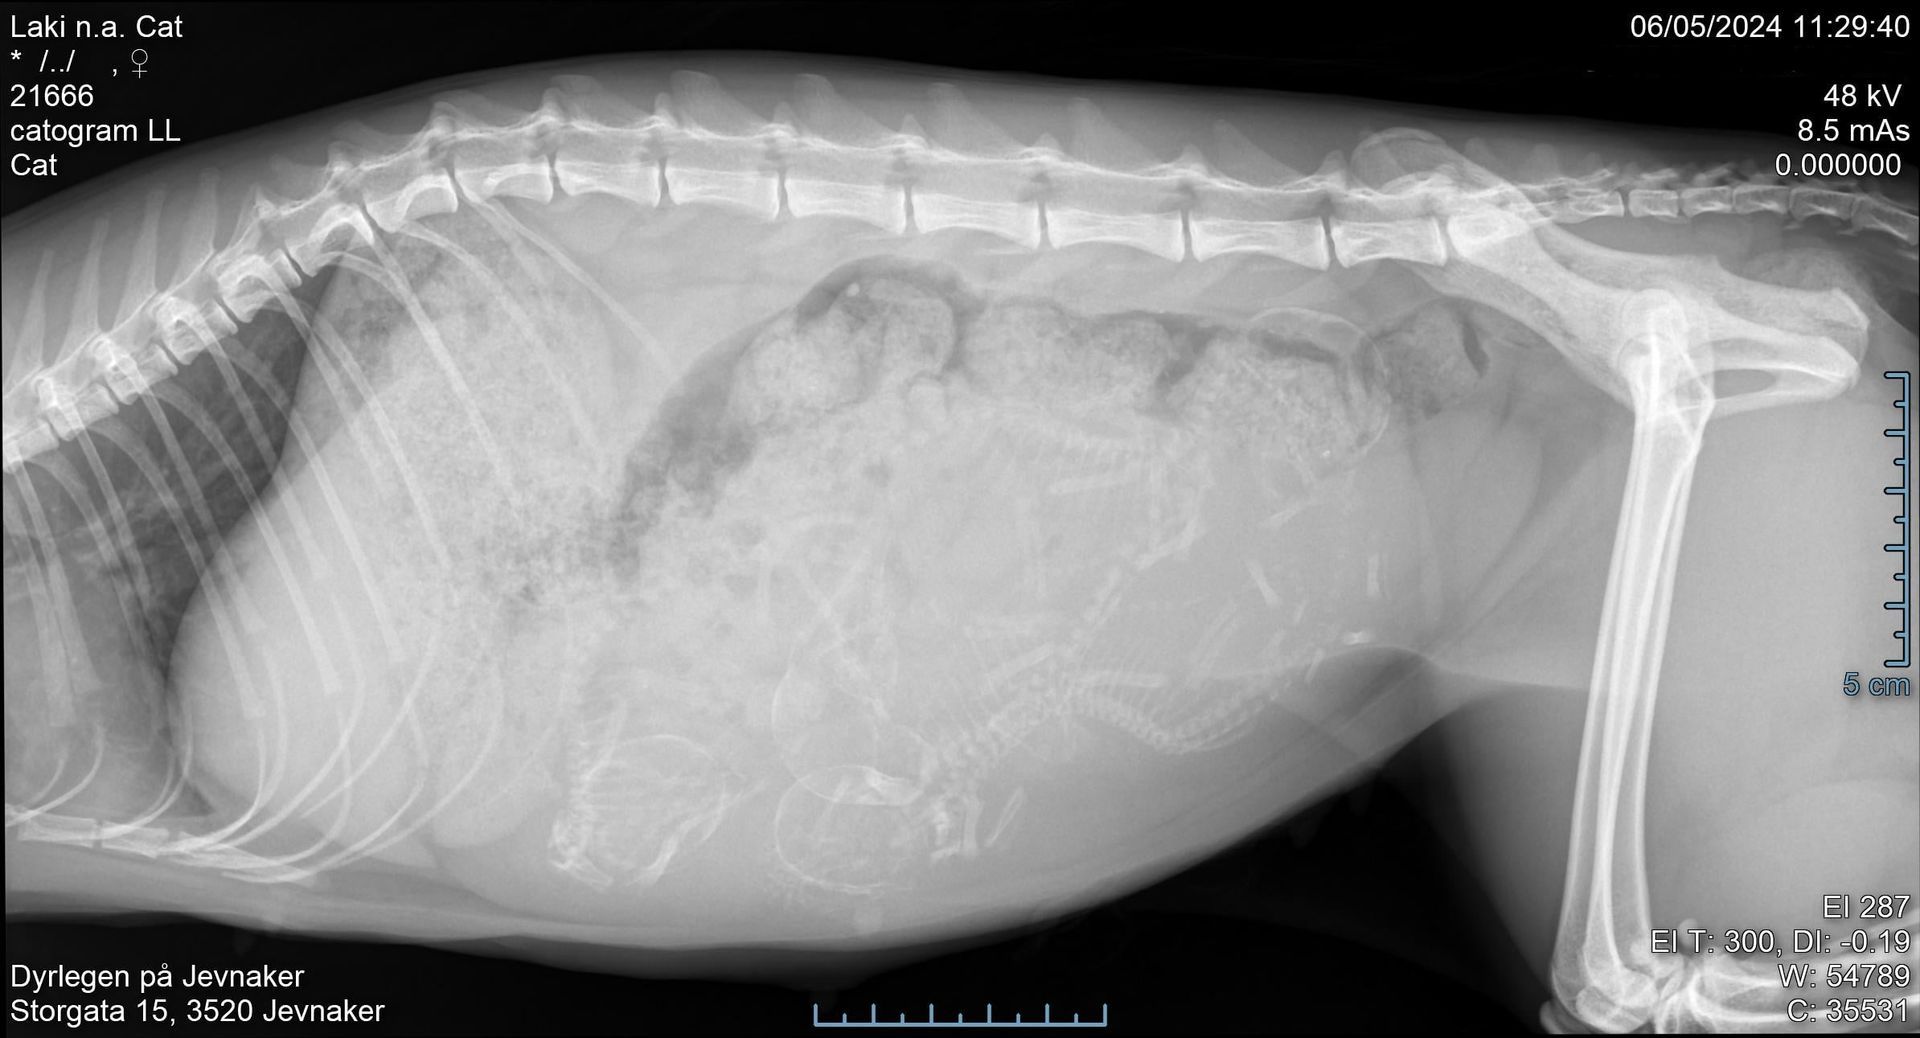

Røntgen & ultralyd

Røntgenundersøkelse er et viktig diagnostisk hjelpemiddel. På klinikken vår har vi digitalt røntgenapparat hvor vi kan avdekke beinbrudd, forkalkninger i ledd, svulster i buk- og brysthule og vi kan også se hvor mange fostre en drektig tispe bærer på. Vi utfører også HD- og AD-røntgenbilder som sendes til NKK for avlesing.

Ved en ultralydsundersøkelse kan vi blant annet avdekke om et dyr er drektig, om det foreligger en livmorbetennelse eller en urinstein.